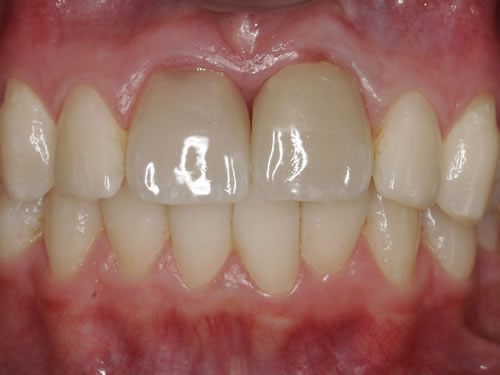

Eine besondere Herausforderung ist die Oberkieferfrontzahnregion. Der Wunsch nach einem perfekten Resultat ist geradezu selbstverständlich. Jeder möchte große, weiße Zähne und ein gesundes, reizloses Zahnfleisch besitzen (Abb. 3.30).

Abb. 3.30: Perfektes Resultat einer Versorgung.